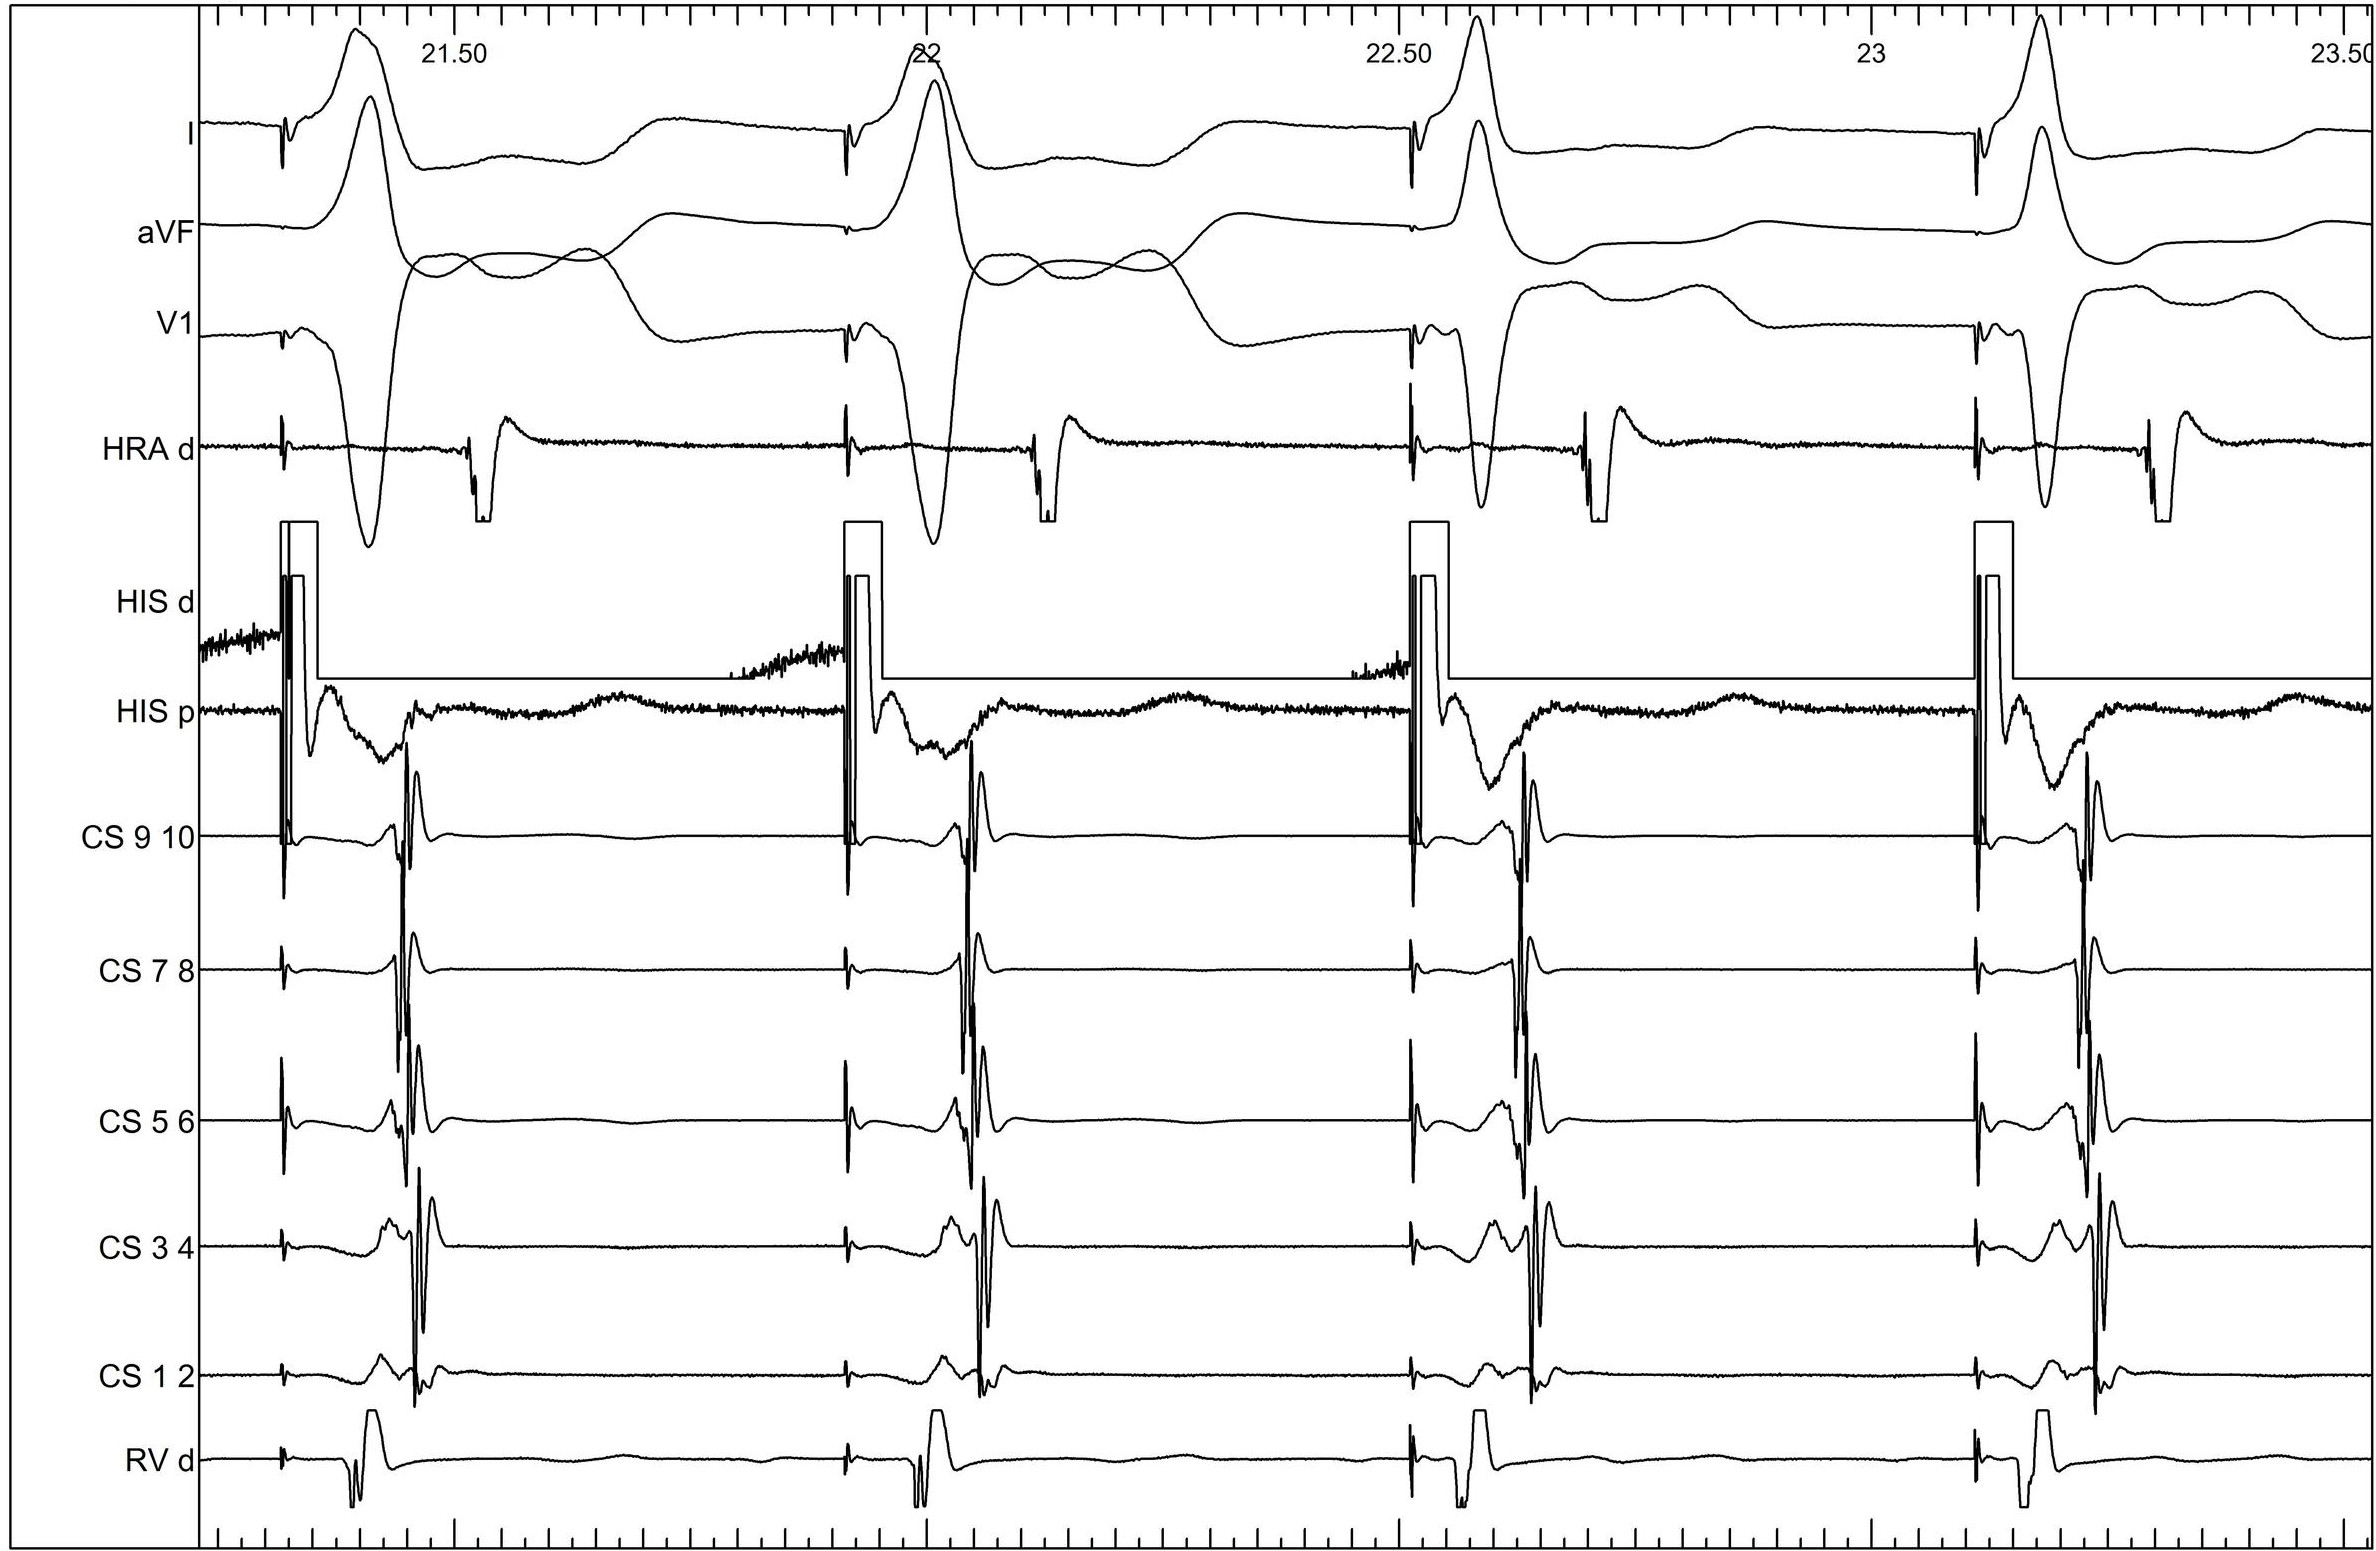

Ventricular extrastimulus

03_v_extra.jpg